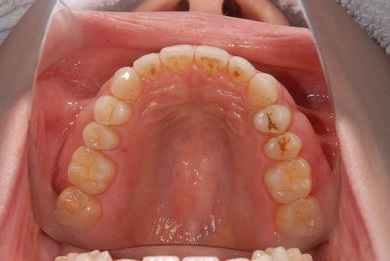

インプラントの症例写真 IMPLANT

インプラント治療

| 性別/年齢 | 女性 / 29歳 | ||||||||||||||||||||||||||||||||

| 主訴 | インプラント治療と、親知らずの抜歯の相談。なるべく安価で、短期間で終了して欲しい。 | ||||||||||||||||||||||||||||||||

| 治療方針 | 欠損部分をインプラント治療にて、機能的・審美的回復を行う。 | ||||||||||||||||||||||||||||||||

| 治療内容 | インプラント1本、メタルボンドセラミッククラウン1本 | ||||||||||||||||||||||||||||||||

| 総治療費 | 252,000円 | ||||||||||||||||||||||||||||||||

| 治療期間 | 11ヶ月 |